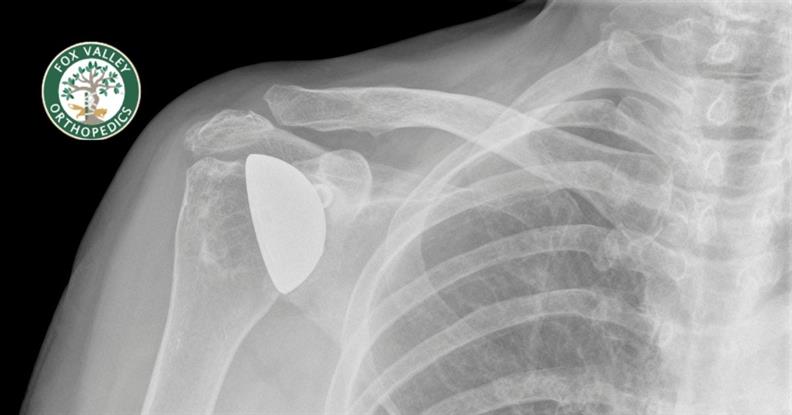

Imaging studies detect what the naked eye cannot see. Say you’ve just sustained a fracture – you likely know you’ve broken ...